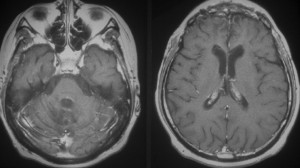

ジャーミノーマには好発部位というものがあります,神経下垂体,松果体,大脳基底核などですが,腫瘍塊を形成しないで周囲脳組織に浸潤伸展しているだけという画像所見をみることがあります。多くは浸潤形態が脳室壁に沿う subependymal infiltrationという特徴からジャーミノーマと画像診断できるのですが,原発部位に腫瘍塊がなくて,視神経交叉や視床あるいは大脳基底核だけに腫瘍があるなどという例もあります。特に注意していただきたいのは,脳組織浸潤が主体で,germinomaとしての腫瘍塊を形成していないことです。正常脳組織内(GFAP陽性)に腫瘍細胞(c-kit陽性)とリンパ球が散在するという病理組織所見になります。

上方が側脳室側です。脳との境にある脳室上衣 ependyumの下に腫瘍細胞が這うように浸潤しています。そこから血管周囲 Virchow-Robin spaceを通って脳深部に浸潤しています。

大脳深部(左)と小脳深部(右)には髄質血管に沿って浸潤します。これは髄芽腫などと同様の脳浸潤所見です。